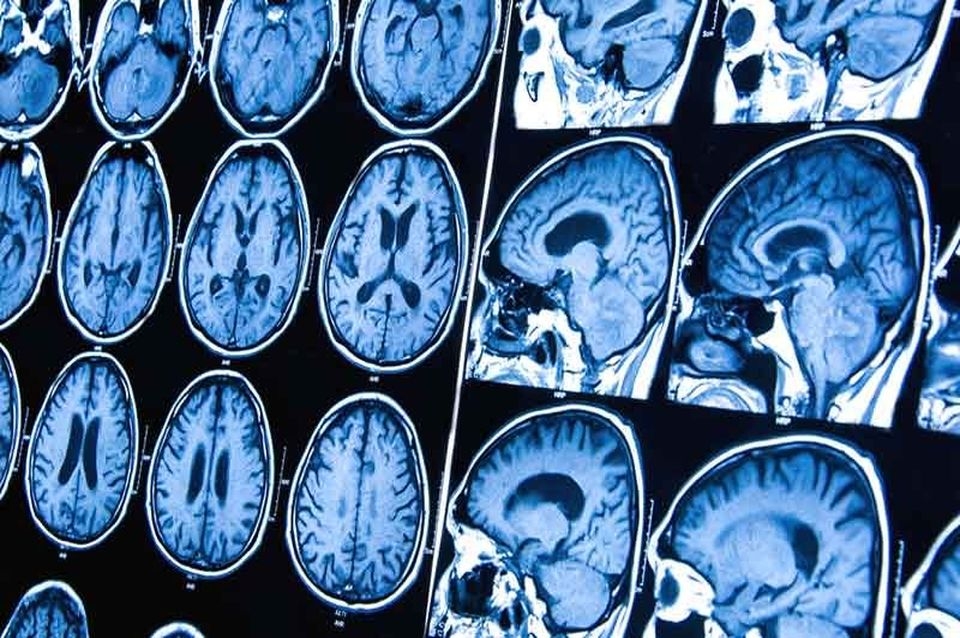

DIAGNÓSTICO

Según la SEOM, el diagnóstico de los tumores cerebrales se realiza mediante la combinación de diferentes pruebas que determinarán la forma, el grado y la extensión del tumor.

El primer paso es la exploración física y neurológica para establecer los síntomas y la afectación neurológica con aspectos como el movimiento de los ojos, la visión, el oído, los reflejos o la coordinación.

El segundo paso son las pruebas radiológicas que permitirán conocer la extensión del tumor, el número de lesiones, tamaño y zonas afectadas. Además, estas pruebas aportarán información relevante, como si el paciente tiene hemorragias, y se utiliza como herramienta complementaria a la valoración de los síntomas. Las pruebas más comunes son el TAC, la resonancia magnética, el PET, el Spect, la punción lumbar y la biopsia.